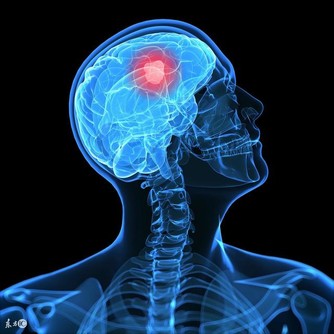

美國研究指出,擁有希臘腳的人患拇囊炎、錘狀指以及背部疾病的風險更高。

因為多數人站立或行走時,腳趾中拇指所受的重量最多,但是對於希臘腳來說,則是第二腳趾會被磨彎、磨平,進而導致腳部疾病的發生。所以擁有希臘腳的人更要注意鞋子的版型,在選擇鞋子時一定要穿起來舒適而且符合腳型,否則會對健康有更多負面的影響喔!